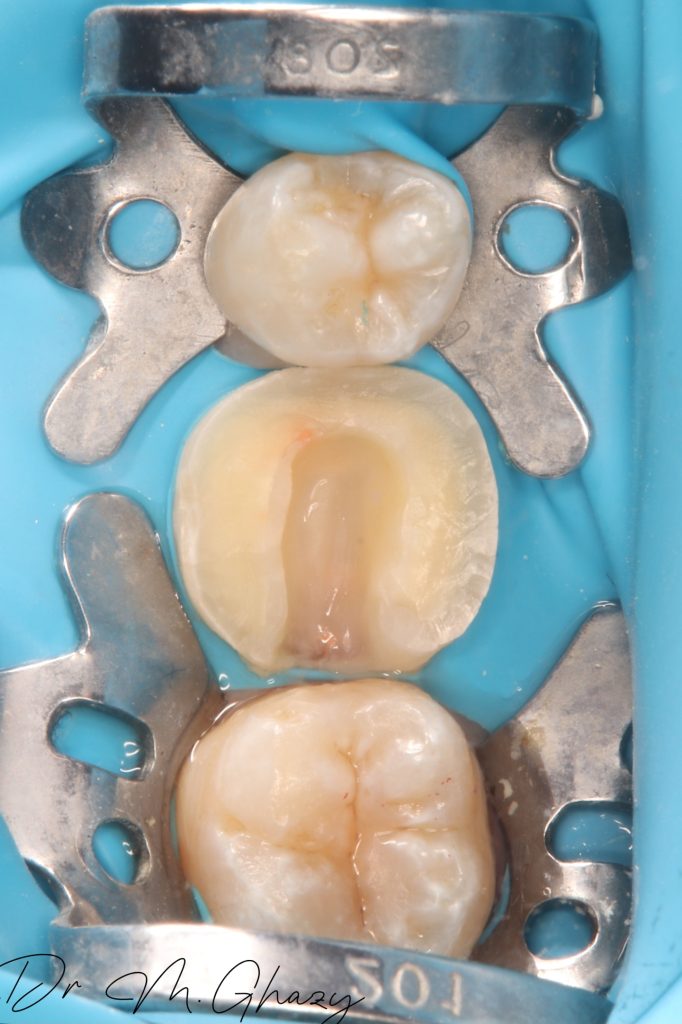

Surface treatment for lithium dislicate by 9.5% HF acid

Chalky White appearance after Rensing and Drying

Silaine coupling agent

Cementation